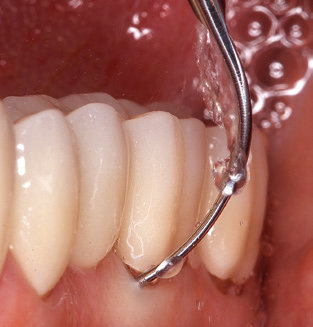

Unerlässlich für die UPT implantat prothetisch versorgter Patienten sind natürlich Arbeitsspitzen für die Reinigung von Implantatoberflächen. Der Implantatreinigungsaufsatz des hier verwendeten Systems zeichnet sich dabei durch eine spitz zulaufende sechskantige konische Form aus. Dieses Design erlaubt ein leichtes atraumatisches Eindringen in die periimplantäre Tasche und zeigt eine gute Reinigungsleistung (Abb. 7).